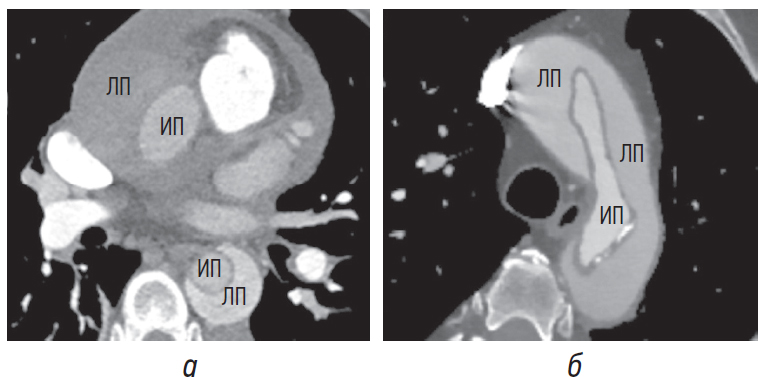

При диссекции аорты давление в ложном просвете превышает или равно давлению в истинном просвете, что приводит к сдавлению последнего (рис. 1, а) вплоть до его коллапса (рис. 1, б) [1, 4, 8].

Рис. 1. Сдавление истинного просвета в восходящем отделе аорты, коллапс истинного просвета в нисходящем отделе аорты. ИП — истинный просвет, ЛП — ложный просвет

Расширение ложного просвета происходит из-за снижения эластичности его тонкой стенки, содержащей только около 1/3 от исходного количества эластина в сравнении с истинным просветом. В конечном итоге натяжение тонкой стенки ложного просвета может приводить к формированию псевдоаневризмы и разрыву ложного просвета. Общая степень дилатации зависит от артериального давления, остаточной толщины стенки и процента окружности стенки, вовлеченного в расслоение [4]. Больший размер является значимым маркером ложного просвета как при острой, так и при хронической диссекции (рис. 2, а, б) [8].

Рис. 2. Ложный просвет больше истинного просвета при острой диссекции (а) и при контроле через 1 год (б). ИП — истинный просвет, ЛП — ложный просвет

Соотношение размеров истинного и ложного просветов при хронической диссекции больше по сравнению с их соотношением при острой диссекции (рис. 3, а, б) вследствие относительно стабильного размера истинного просвета в сочетании с формированием дегенеративной псевдоаневризмы ложного просвета. Разница наиболее значительна дистальнее отхождения левой подключичной артерии и выше уровня отхождения чревного ствола [7]. При этом истинный просвет чаще имеет цилиндрическую или нитевидную форму.

Рис. 3. Отношение размеров истинного и ложного просветов в острый период (а), в хронический период через 1 год (б). ИП — истинный просвет, ЛП — ложный просвет